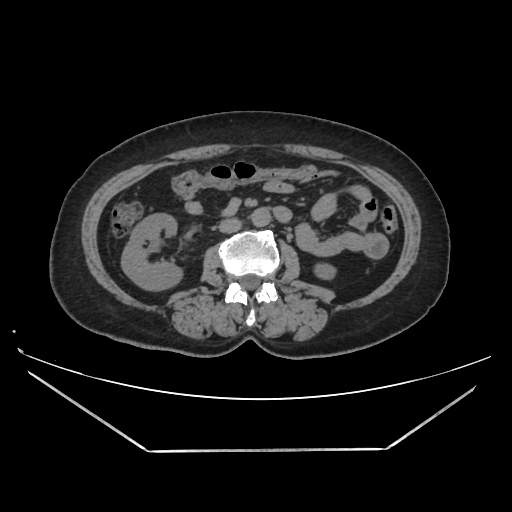

A CT abdomen revealed a left adrenal cortical tumor.

Her abdominal X-ray also reveals a right renal stone although she never complained of renal colic.

CT images: